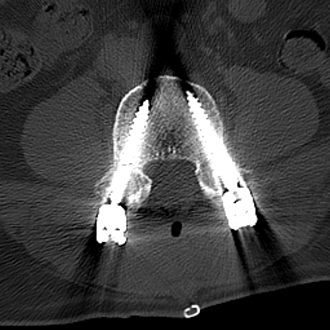

64岁的邱某因“腰痛多年,加重伴左下肢放射痛1月”来到昆山市中医医院脊柱骨科陈勇主任门诊就诊,经对患者的评估后,陈勇主任考虑其为“腰椎间盘突出症、腰椎椎管狭窄症”,随即安排住院治疗。

入院后,陈勇主任在科室组织了病例讨论并表示:常规保守治疗只能缓解症状无法从根本上解决病根。目前,患者已保守治疗1月,症状未见明显缓解,且进行性加重。影像学可见腰椎间盘突出伴椎管狭窄严重程度高,有明确的手术指征,结合患者及其家属的意愿,选择腰椎后路减压植骨融合内固定术。

▲术前MRI

然而患者需行多节段腰椎融合

如何规避神经损伤风险?